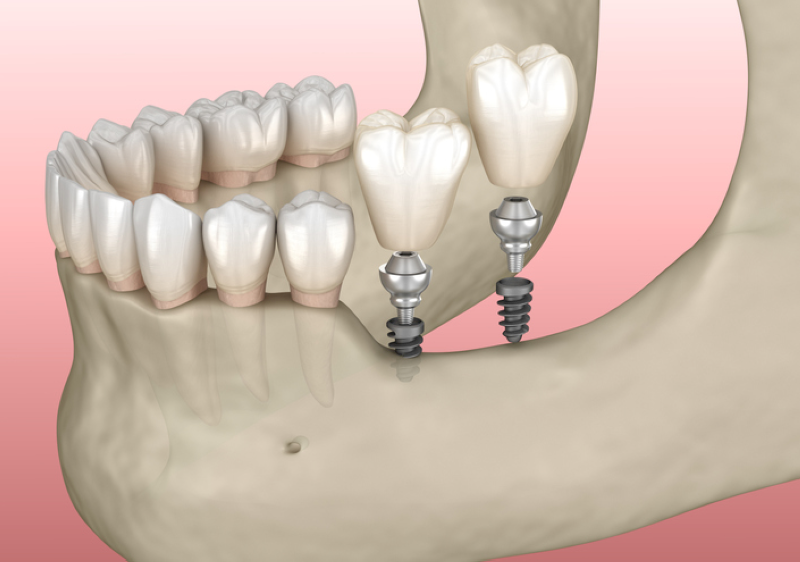

Trồng răng Implant là phương pháp cấy một chân răng nhân tạo vào vị trí của răng thật đã mất, giúp cải thiện thẩm mỹ đồng thời mang lại cảm giác ăn nhai thoải mái cho người mất răng. Bài viết dưới đây sẽ cung cấp thông tin cơ bản xoay quanh phương pháp trồng răng Implant, các yếu tố quan trọng cô chú/anh chị cần biết và chi phí của phương pháp này.